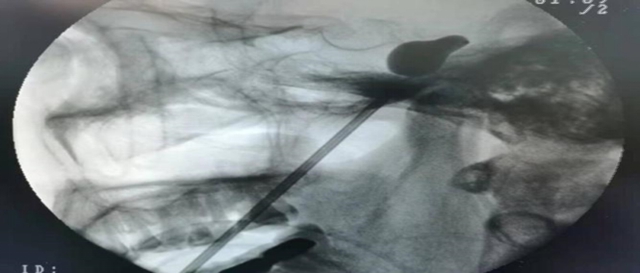

经皮穿刺三叉神经微创球囊压迫术(pmc):患者在全麻下,经c形臂的引导,从面部皮肤穿刺达到三叉神经出颅腔的部位——卵圆孔,以球囊导管置入麦克氏囊,通过球囊扩张适度压迫三叉神经半月节,充分阻断三叉神经的痛觉神经元,达到治疗的目的。

微球囊

梨